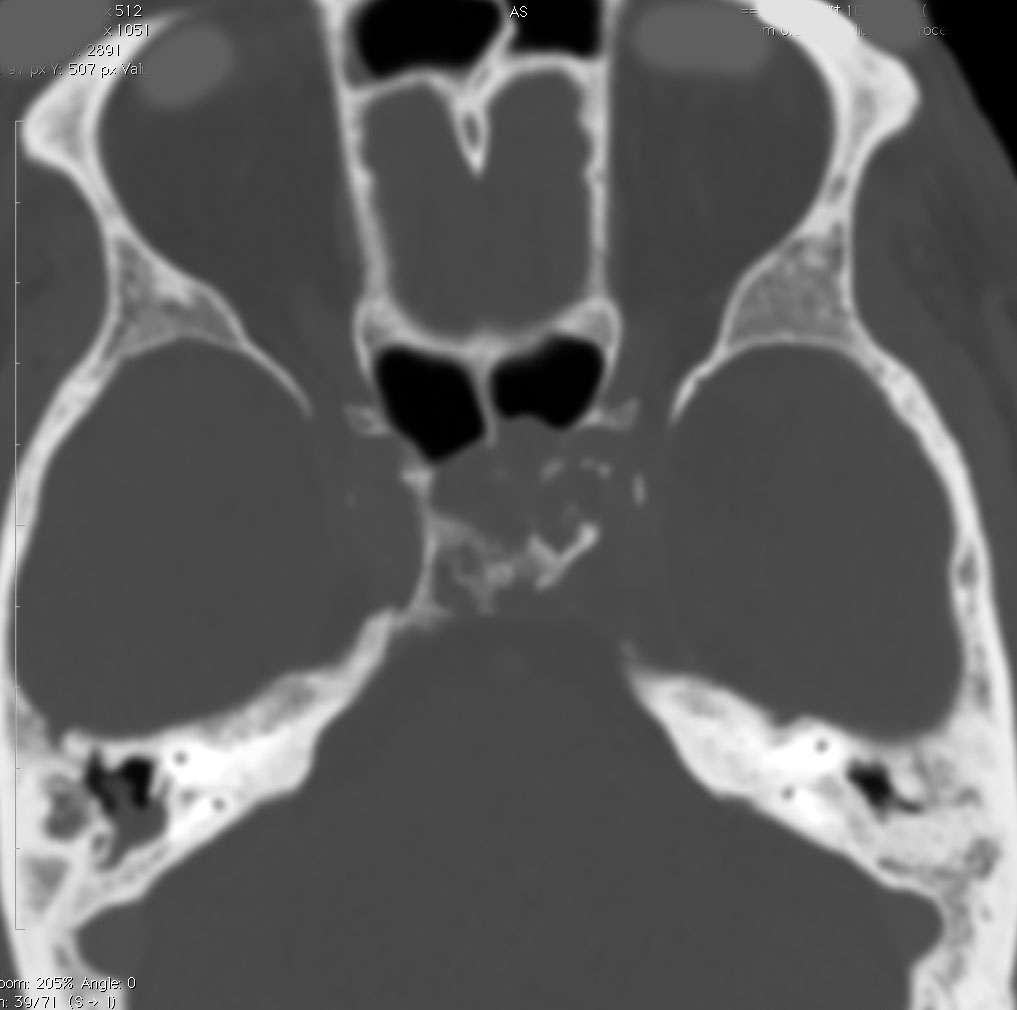

巨大なエコルドーシス・フィサリフォラ

骨をみているCTです。鞍背からsphenooccipital synchondrosisまでの斜台骨皮質が失われています。かなり特徴的な所見です。

T2強調画像とFLAIR像です。FLAIRでは髄液より高信号となります。のう胞様の膨らみを有します。脊索腫と異なり,expanding mass と表現されます。